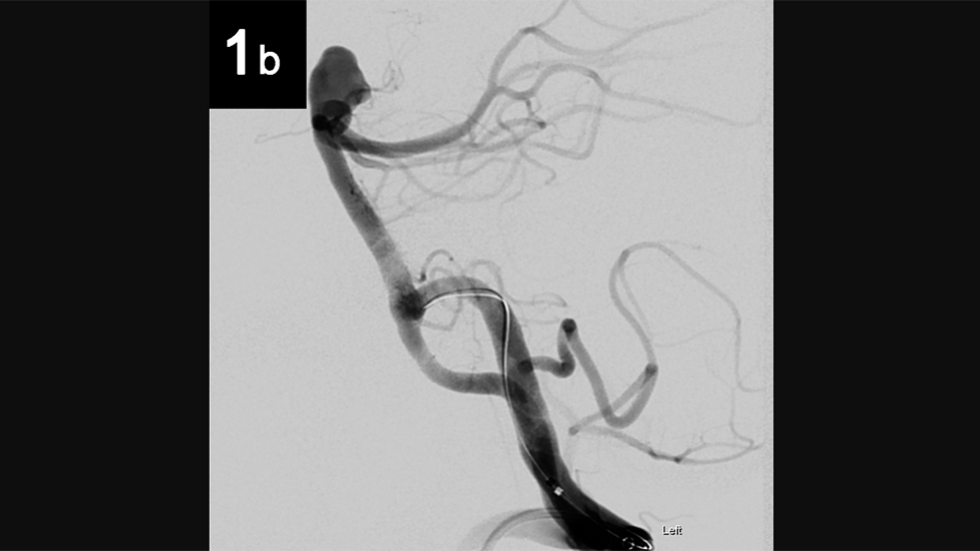

Intrasaccular: 1a

Intrasaccular

Intrasaccular: 2a

2 of 6

Intrasaccular: 1b

4 of 6

Intrasaccular: 2b

5 of 6

Intrasaccular: 3b

6 of 6